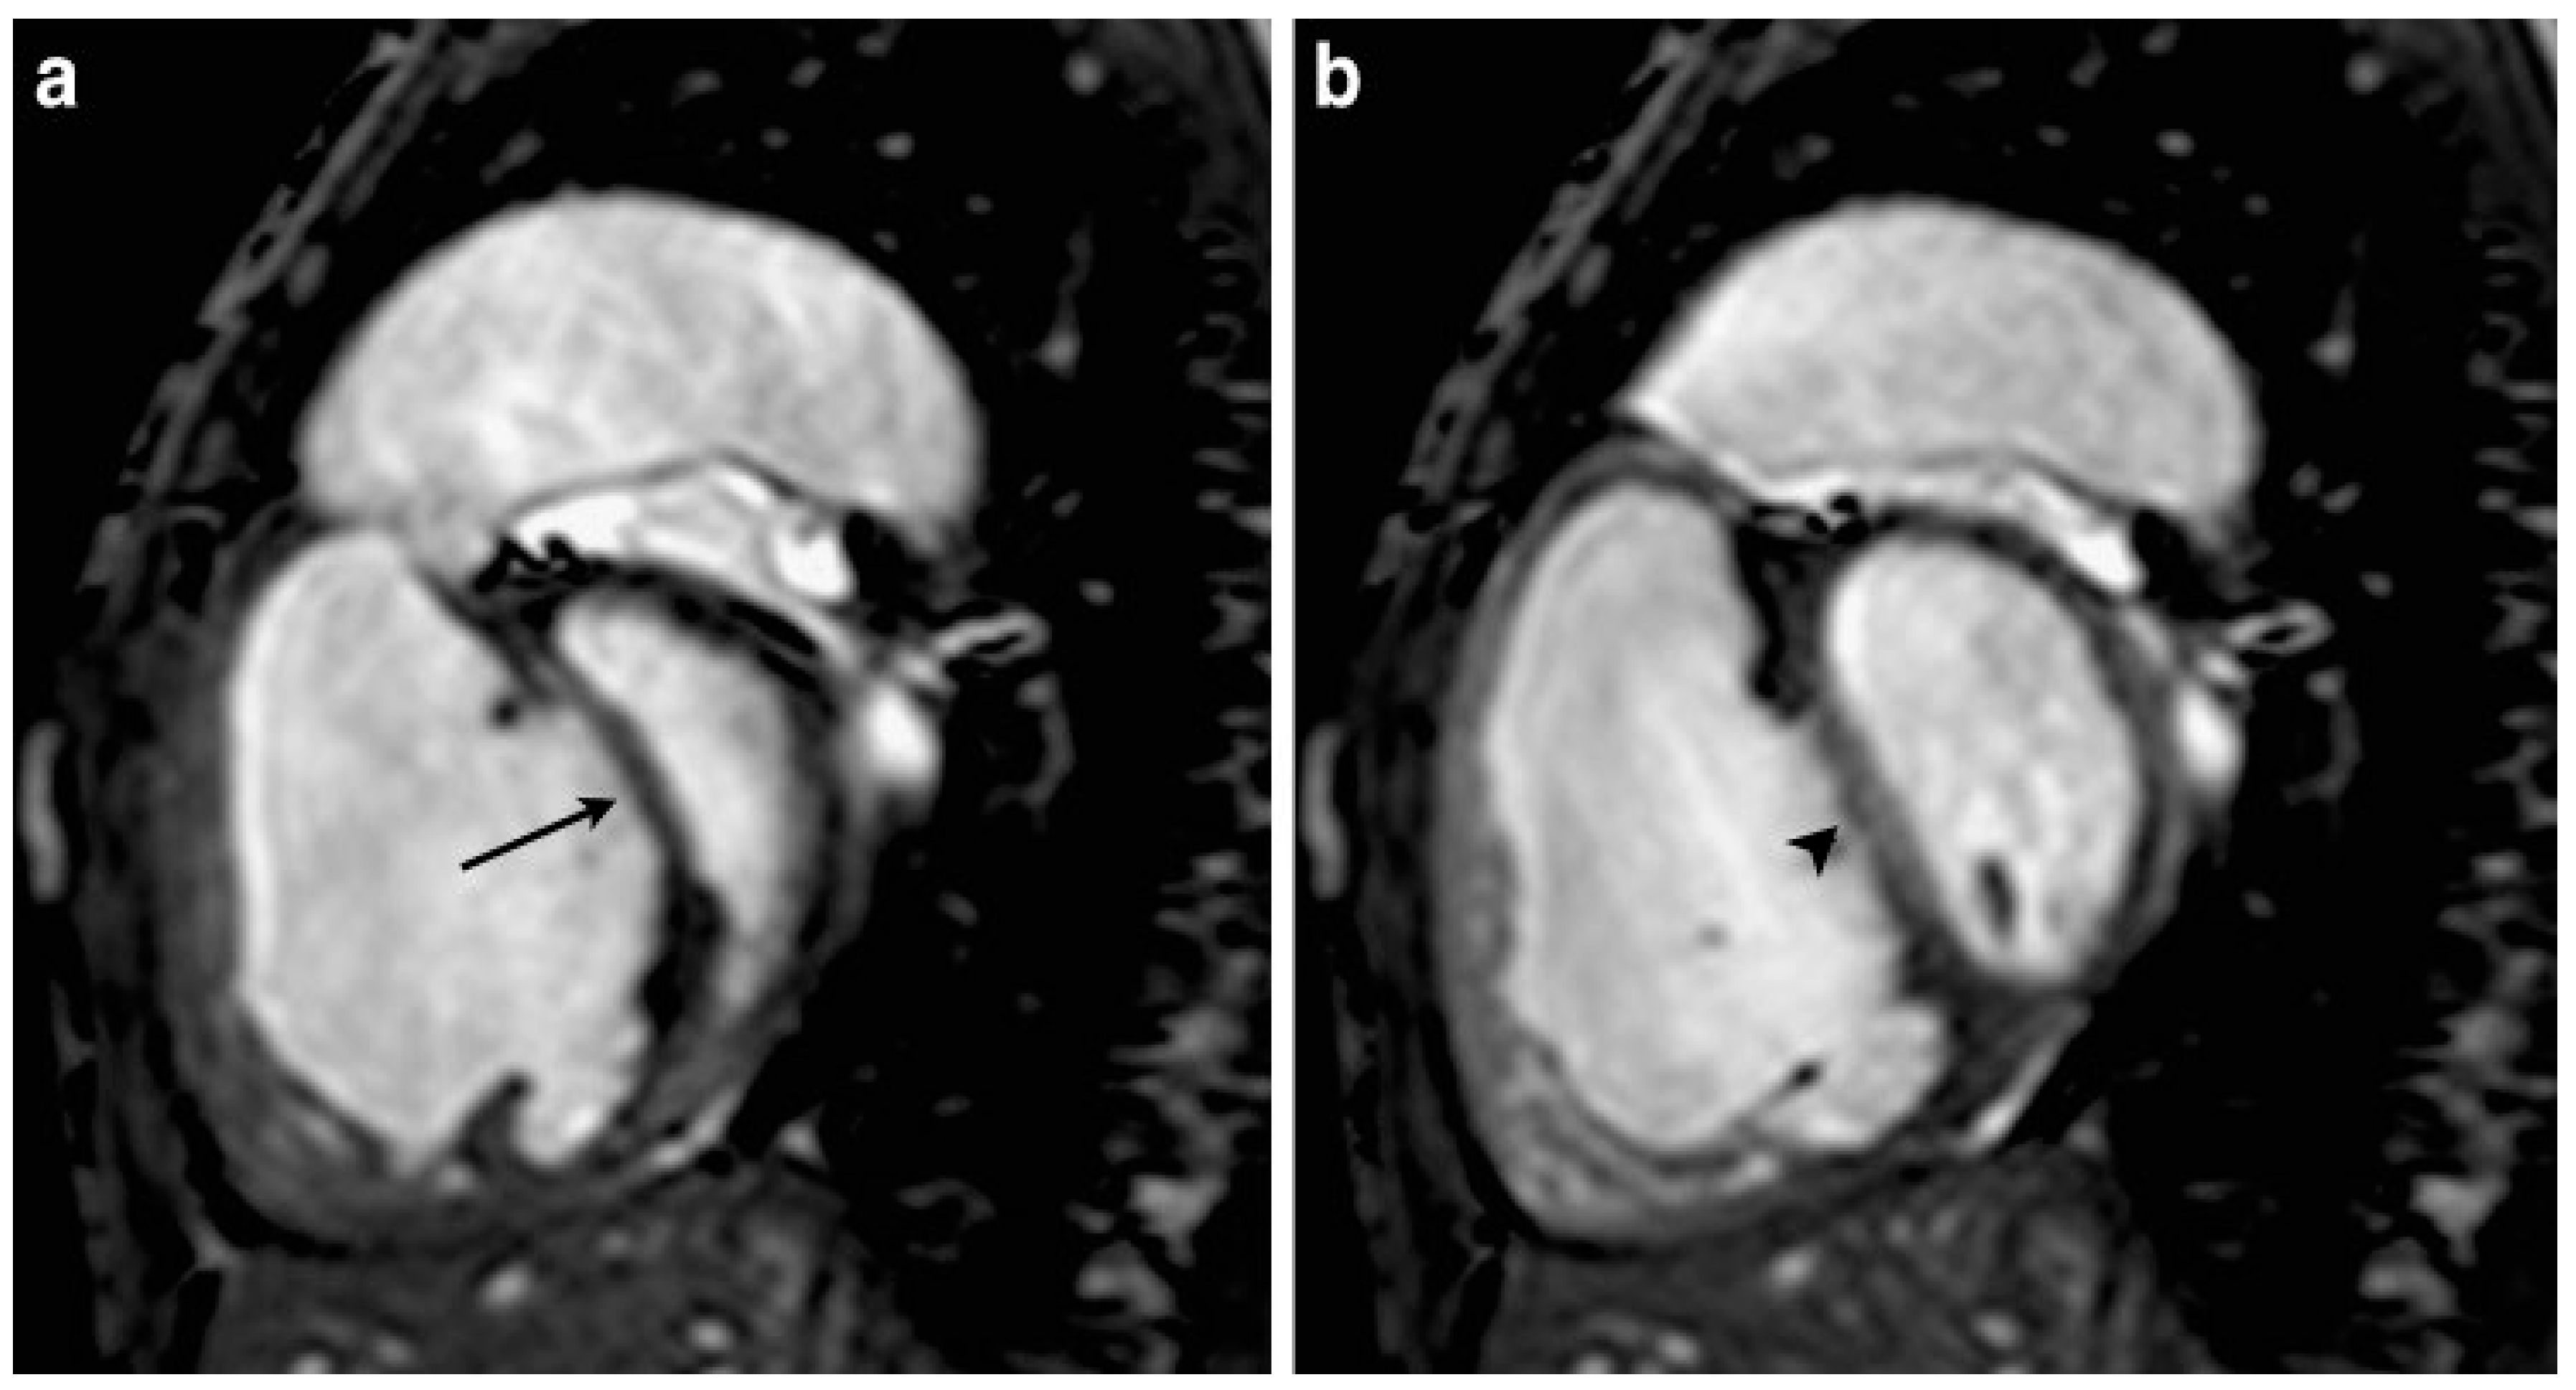

4. Imaging Characteristics on MRI

| 61/Male | Cardiac MRI | Flattened or left-bowing septum during diastole; eccentricity index abnormal | Severe idiopathic pulmonary hypertension [23] |

| 18/Male | Cardiac MRI | Hypertrophied right ventricle and septal leftwards bowing during early diastole | severe idiopathic pulmonary hypertension [23] |